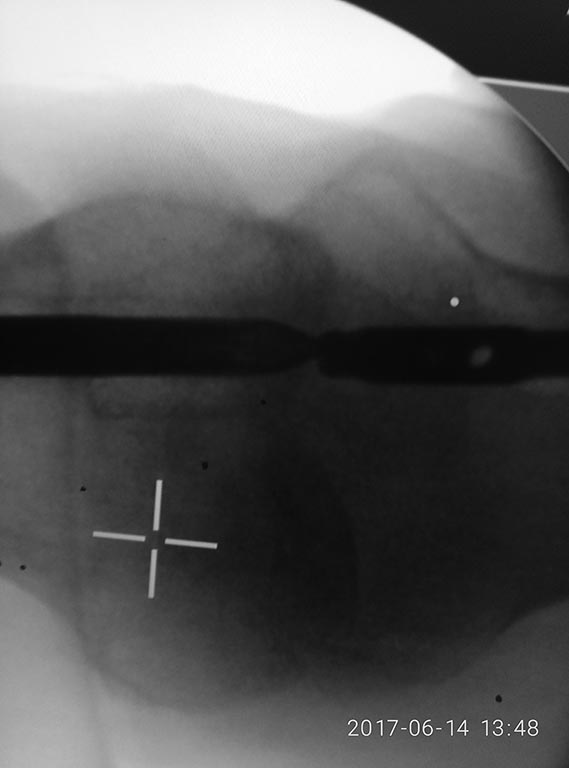

Доброе утро, коллеги! Фикшен с бедра удалили, сидел очень плотно.

На ортопедическом столе уложили, ногу согнули, как на ретроградное

бедро, артротомия, релиз 4-главой, увеличили обьем движений. Далее

попытка выбить плечевым, голенным штифтом не сильно имела успех. Стоял

на своем. Проксимально по направителю рассверлили канал развертками

11,12. В итоге взяли 11 фемор санатметал, несколько ударов, и он вылетел

из бедра!